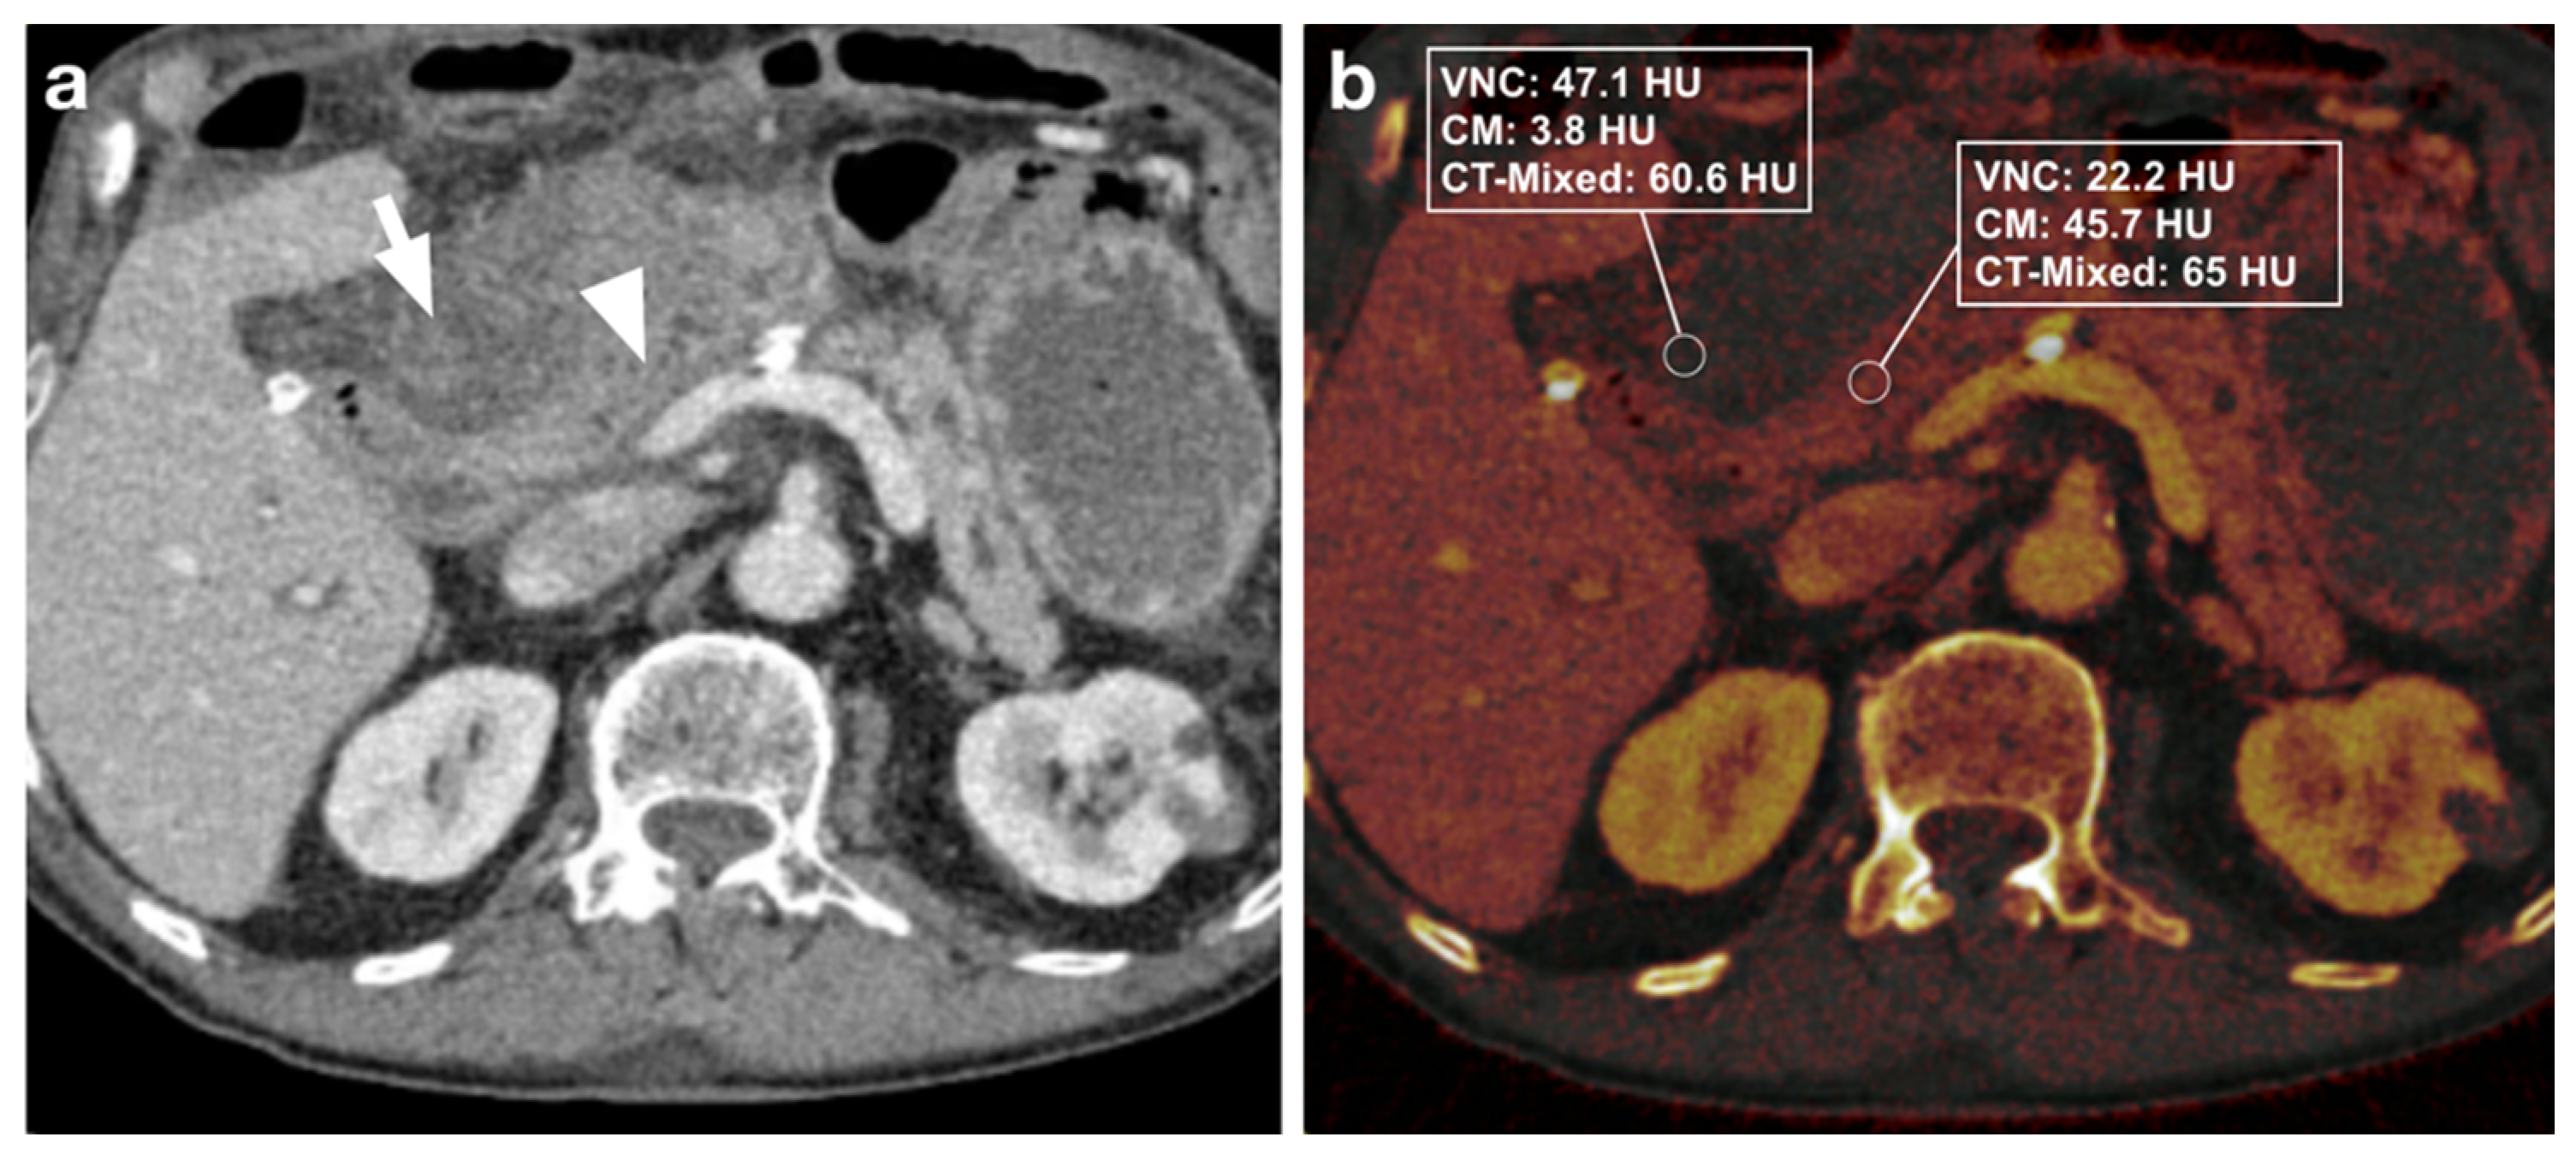

3.2.1. DECT Image Analysis